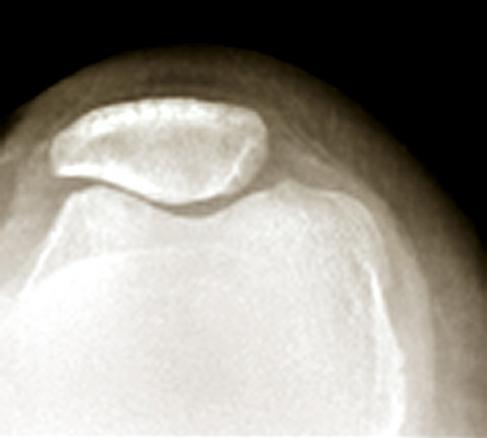

Arthrose fémoro-patellaire

Radiologie d'une arthrose fémoro-patellaire avec rotule retrouvée translatée en dehors